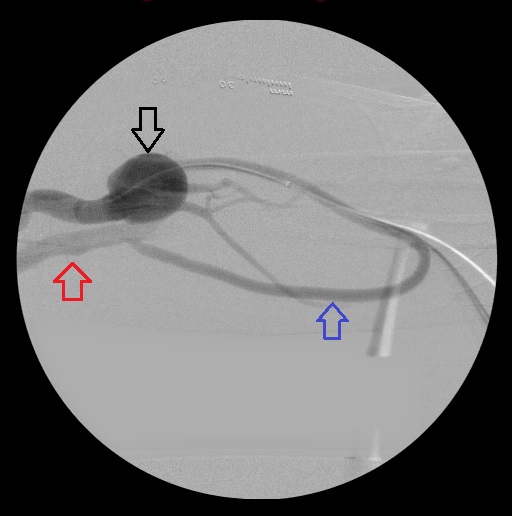

Left forearm loop graft angiogram: Large aneurysm of the distal left brachial artery (black arrow); the loop graft (blue arrow); the left brachial vein (red arrow).